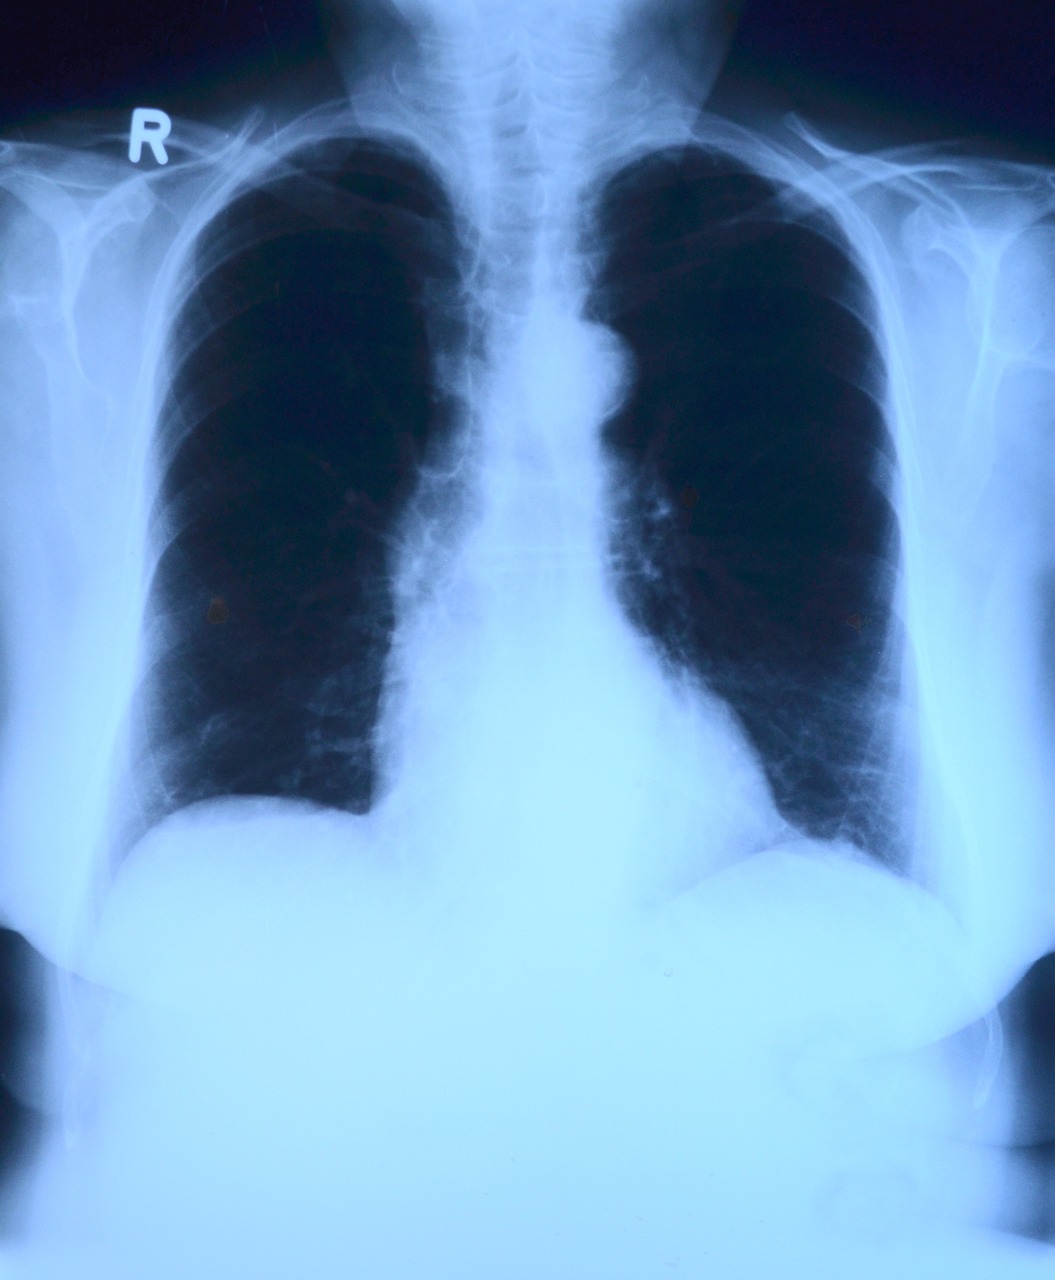

결핵의 증상

결핵의 증상은 다양하고, 감염된 부위와 개인의 면역력에 따라 다를 수 있습니다. 주로 폐결핵이 가장 흔하게 나타나지만, 다른 부위에도 결핵이 발생할 수 있습니다.

<폐결핵 증상>

- 지속적인 많은 기침

- 가래 또는 피가 섞인 가래

- 가슴 통증

- 호흡곤란

- 체중 감소

- 피로 또는 피곤함

- 발열 및 땀 증가

4. 결핵 검진

결핵에 노출되거나 결핵 증상이 있는 경우, 의료진과 상담하여 적절한 검사와 조치를 받는 것이 중요합니다. 결핵은 조기에 발견되고 치료되면 치유될 수 있는 질병입니다.